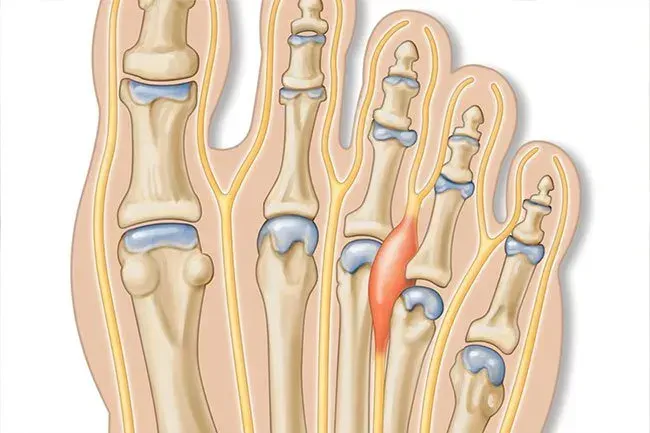

Névrome de Morton

Il s'agit d'une condition du pied très courante. Jusqu'à une personne sur trois peut l'avoir. Les symptômes incluent la douleur dans la partie avant de votre pied ou un sentiment que vous marchez sur un rocher ou un marbre. Cela se produit bien plus souvent chez les femmes plus âgées et chez ceux qui portent des talons hauts ou des chaussures avec une boîte à orteils serrée. La commutation de tampons de chaussures et de massage peut aider. Si votre douleur devient sévère, votre médecin peut suggérer des photos de stéroïdes ou une chirurgie.